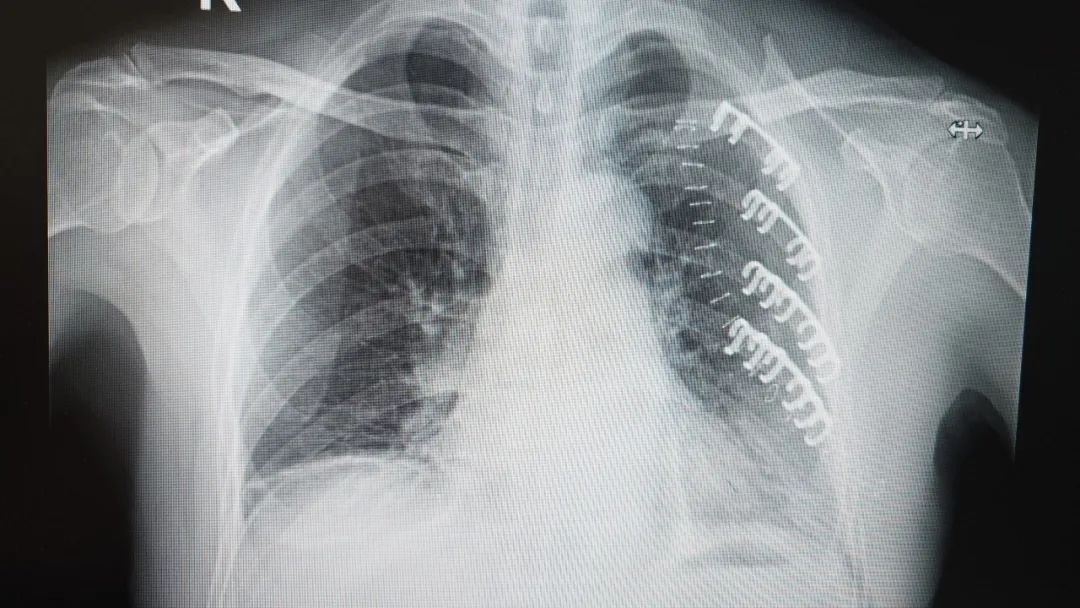

患者術(shù)后CT影像

術(shù)后僅僅2小時,李大爺就能在指導(dǎo)下小口喝下流食。更令人難以置信的是,手術(shù)當(dāng)晚,在醫(yī)護(hù)人員專業(yè)指導(dǎo)和嚴(yán)密監(jiān)護(hù)下,李大爺竟然可以小心翼翼地坐起,并在攙扶下嘗試著地站立活動!“哎呀!真是沒想到!胸口不那么疼了,這么快就能動,感覺像換了個人似的!”病床上的李大爺難掩激動,向?qū)O振教授連連道謝。

孫振教授介紹,“對于多發(fā)移位性肋骨骨折,傳統(tǒng)保守治療需長期臥床,易引發(fā)并發(fā)癥。而記憶合金內(nèi)固定術(shù)能立即穩(wěn)定胸廓,且肋骨骨板生物相容性佳,無需取出,避免了二次創(chuàng)傷,顯著提高老年患者的生活質(zhì)量。該技術(shù)適用于多發(fā)、錯位明顯的肋骨骨折,能有效防止骨折斷端刺破肺組織?!?/span>